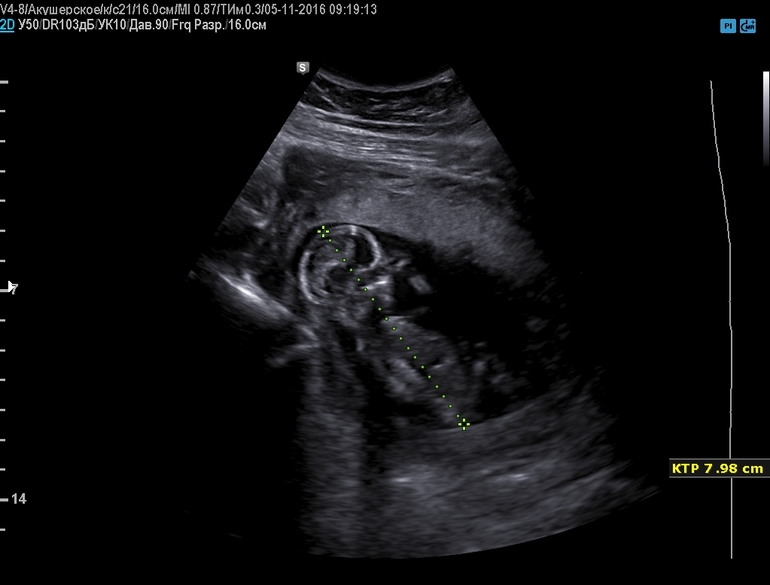

Вопросы про УЗИ, обследования и анализы: что, где, как, когда?срок 13 недель и 6 дней на узи сказали 80% что это мальчик.А вы что думаете?

На таком сроке пол еще не виден) В очень редких случаях можно что-то предположить по половом бугорку, вернее его форме, но это все равно "вилами по воде" и то, что обведено на фото - совсем не половой бугорок ;) Не торопите события)

да вот я тоже думаю что рано еще, а врач узи говорит что 80% что это мальчик и вот как раз этот бугорок мне и обвила в доказательство)))

Где то встречала, что если бугорок стоячий, то мальчик, а если лежачий, то девочка